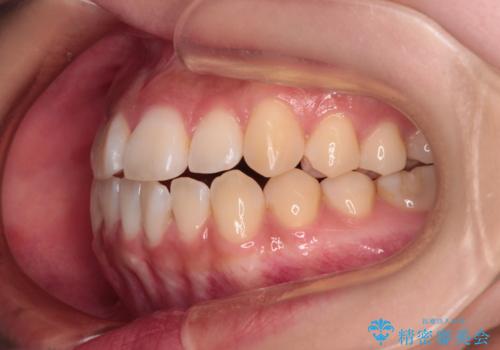

上下非接触の前歯 口元の突出感を改善する抜歯矯正

- 口元の突出感と上下前歯のズレを気にして来院された患者様です。

舌の突出癖により上下の前歯は非接触となっている状態でした。

舌のトレーニングをしっかりと行ってくださり、1年半という非常に短い期間で仕上げることができました。